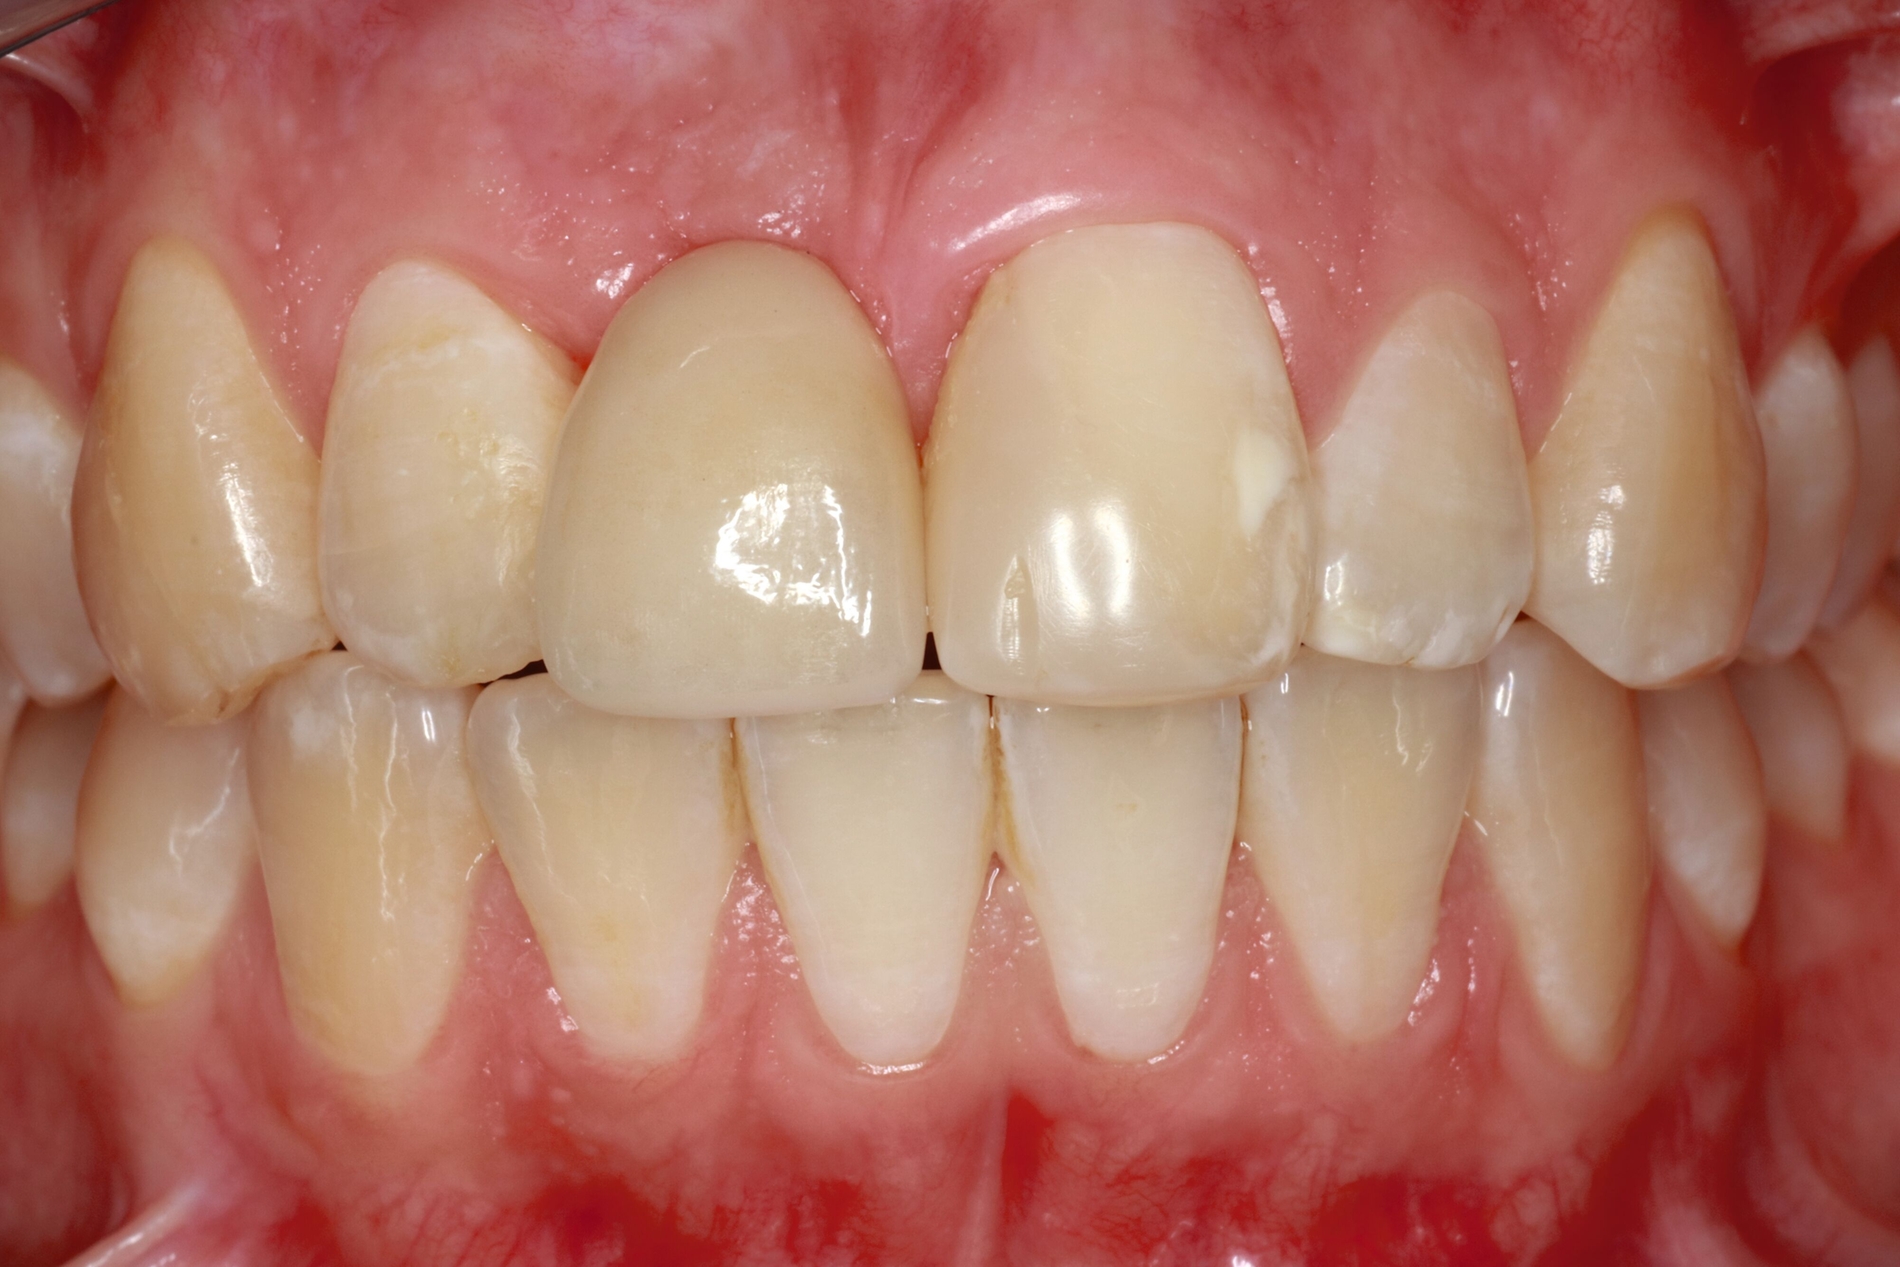

Alternativ dazu bietet sich die Koronalverlagerung der Defektgrenze mit gleichzeitiger Wiederherstellung der biologischen Breite durch eine kieferorthopädische (siehe Teil 5 der Fortbildung „Dentales Trauma“: Kieferorthopädische Aspekte) oder die chirurgische Extrusion an (Abbildung 2).